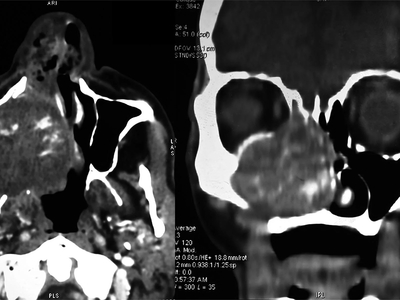

An “enormous” gossypiboma, which is a mass inside the body composed of retained surgical gauze or sponge surrounded by an inflammatory foreign body reaction.